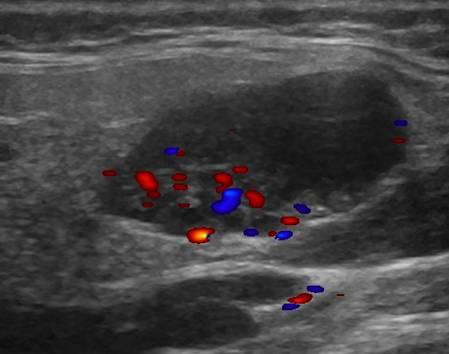

U tuyến nước bọt

» Thông tin: Nam giới – 71 tuổi.

» Lâm sàng: Khối vùng mang tai.

# U lympho tuyến nang (U Warthin) tuyến nước bọt mang tai.